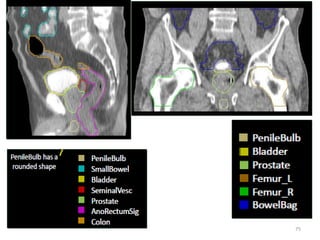

How MR Imaginghelps in contouring rectal cancers • To assess bulky polyps >5mm thick • Initial assessment of disease remote from the lumen within entire mesorectum • Identification of pelvic sidewall disease • Identify site location of stalk or invasive border and relationship to puborectalis sling, peritoneal reflection, mesorectal or intersphincteric border • Identification of high risk patients with extramural venous invasion 68

Rectal Cancer RadiotherapyContouring Guideline for clinical target volumes (CTV) for neoadjuvant chemoradiotherapy in locally advanced rectal cancer: gross tumor, peri-rectal, pre-sacral, internal iliac and external iliac. NTUH practice: • GTV: main tumor mass + involved lymph nodes • CTV: – GTV with 15 mm expansion – Distal 20 mm margin to GTV for CTV – Vessels with 7 mm expansion – Contour CTV to include mesorectum and pre-sacrum – Avoid bone and small bowel Int J Radiat Oncol Biol Phys. 2009 Jul 1;74(3):824-30. doi: 10.1016/j.ijrobp.2008.08.070.

RTOG CONSENSUS PANELRECOMMENDATIONS • Risk volumes defined as CTVs: these were local and nodal. • Local CTV included mesorectum, presacrum, scar tissue and anastomosis. • Nodal CTV included perirectal, iliac (external and internal) and inguinal. • Nodal CTVs: – CTVA: internal iliac, presacral and peri-rectal – CTVB: external iliac – CTVC: inguinal 73 https://www.rtog.org/CoreLab/ContouringAtlases/Anorectal.aspx; Myerson et al. IJROBP 2009